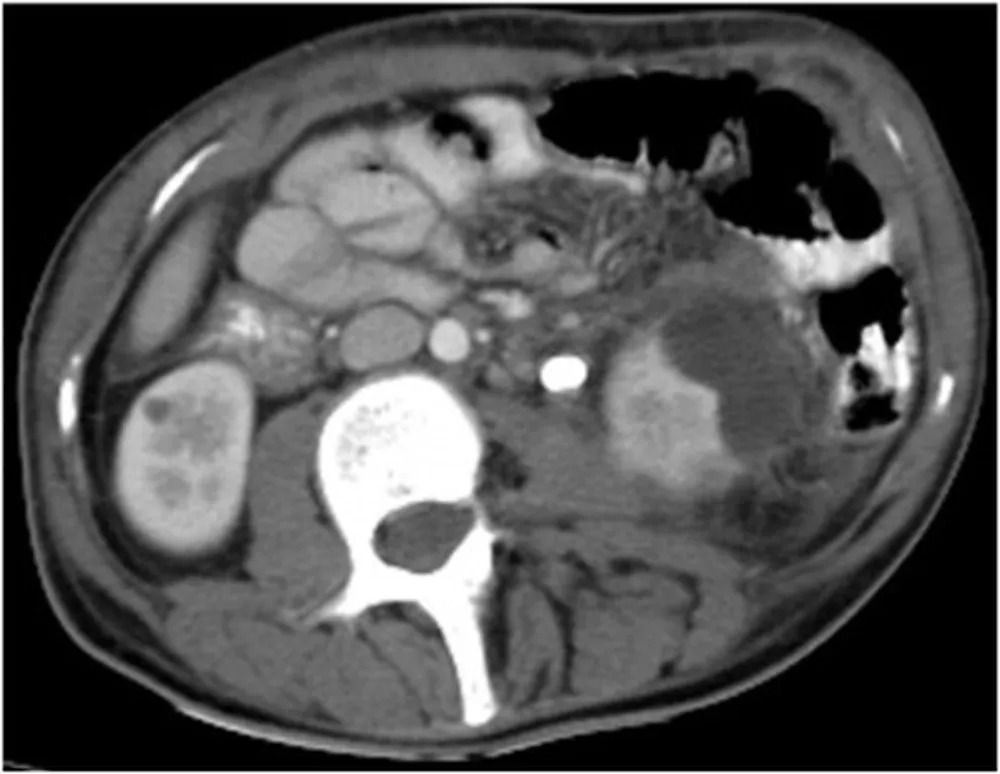

Os sintomas da mulher, que incluíam febre, calafrios, dores abdominais e vômitos, levaram-na ao pronto-socorro. Uma tomografia computadorizada revelou a pedra, que estava pressionando a bexiga da mulher e causando ainda mais perdas de urina.